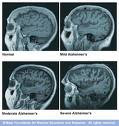

Farias and her colleagues divided everyday functioning into seven cognitive "domains:" memory, language, semantic or factual knowledge, visual and spatial abilities, planning, organization and divided attention.

An original list of 138 items was eventually culled to 39, which was then tested in 576 older adults: 174 of whom were cognitively normal, 126 who had mild cognitive impairment (MCI), and 276 who had been diagnosed with dementia.

Not only did the instrument confirm established diagnoses, it was also able to distinguish people with MCI from those with full-blown dementia, meaning it was able to pick up on subtle differences in function.